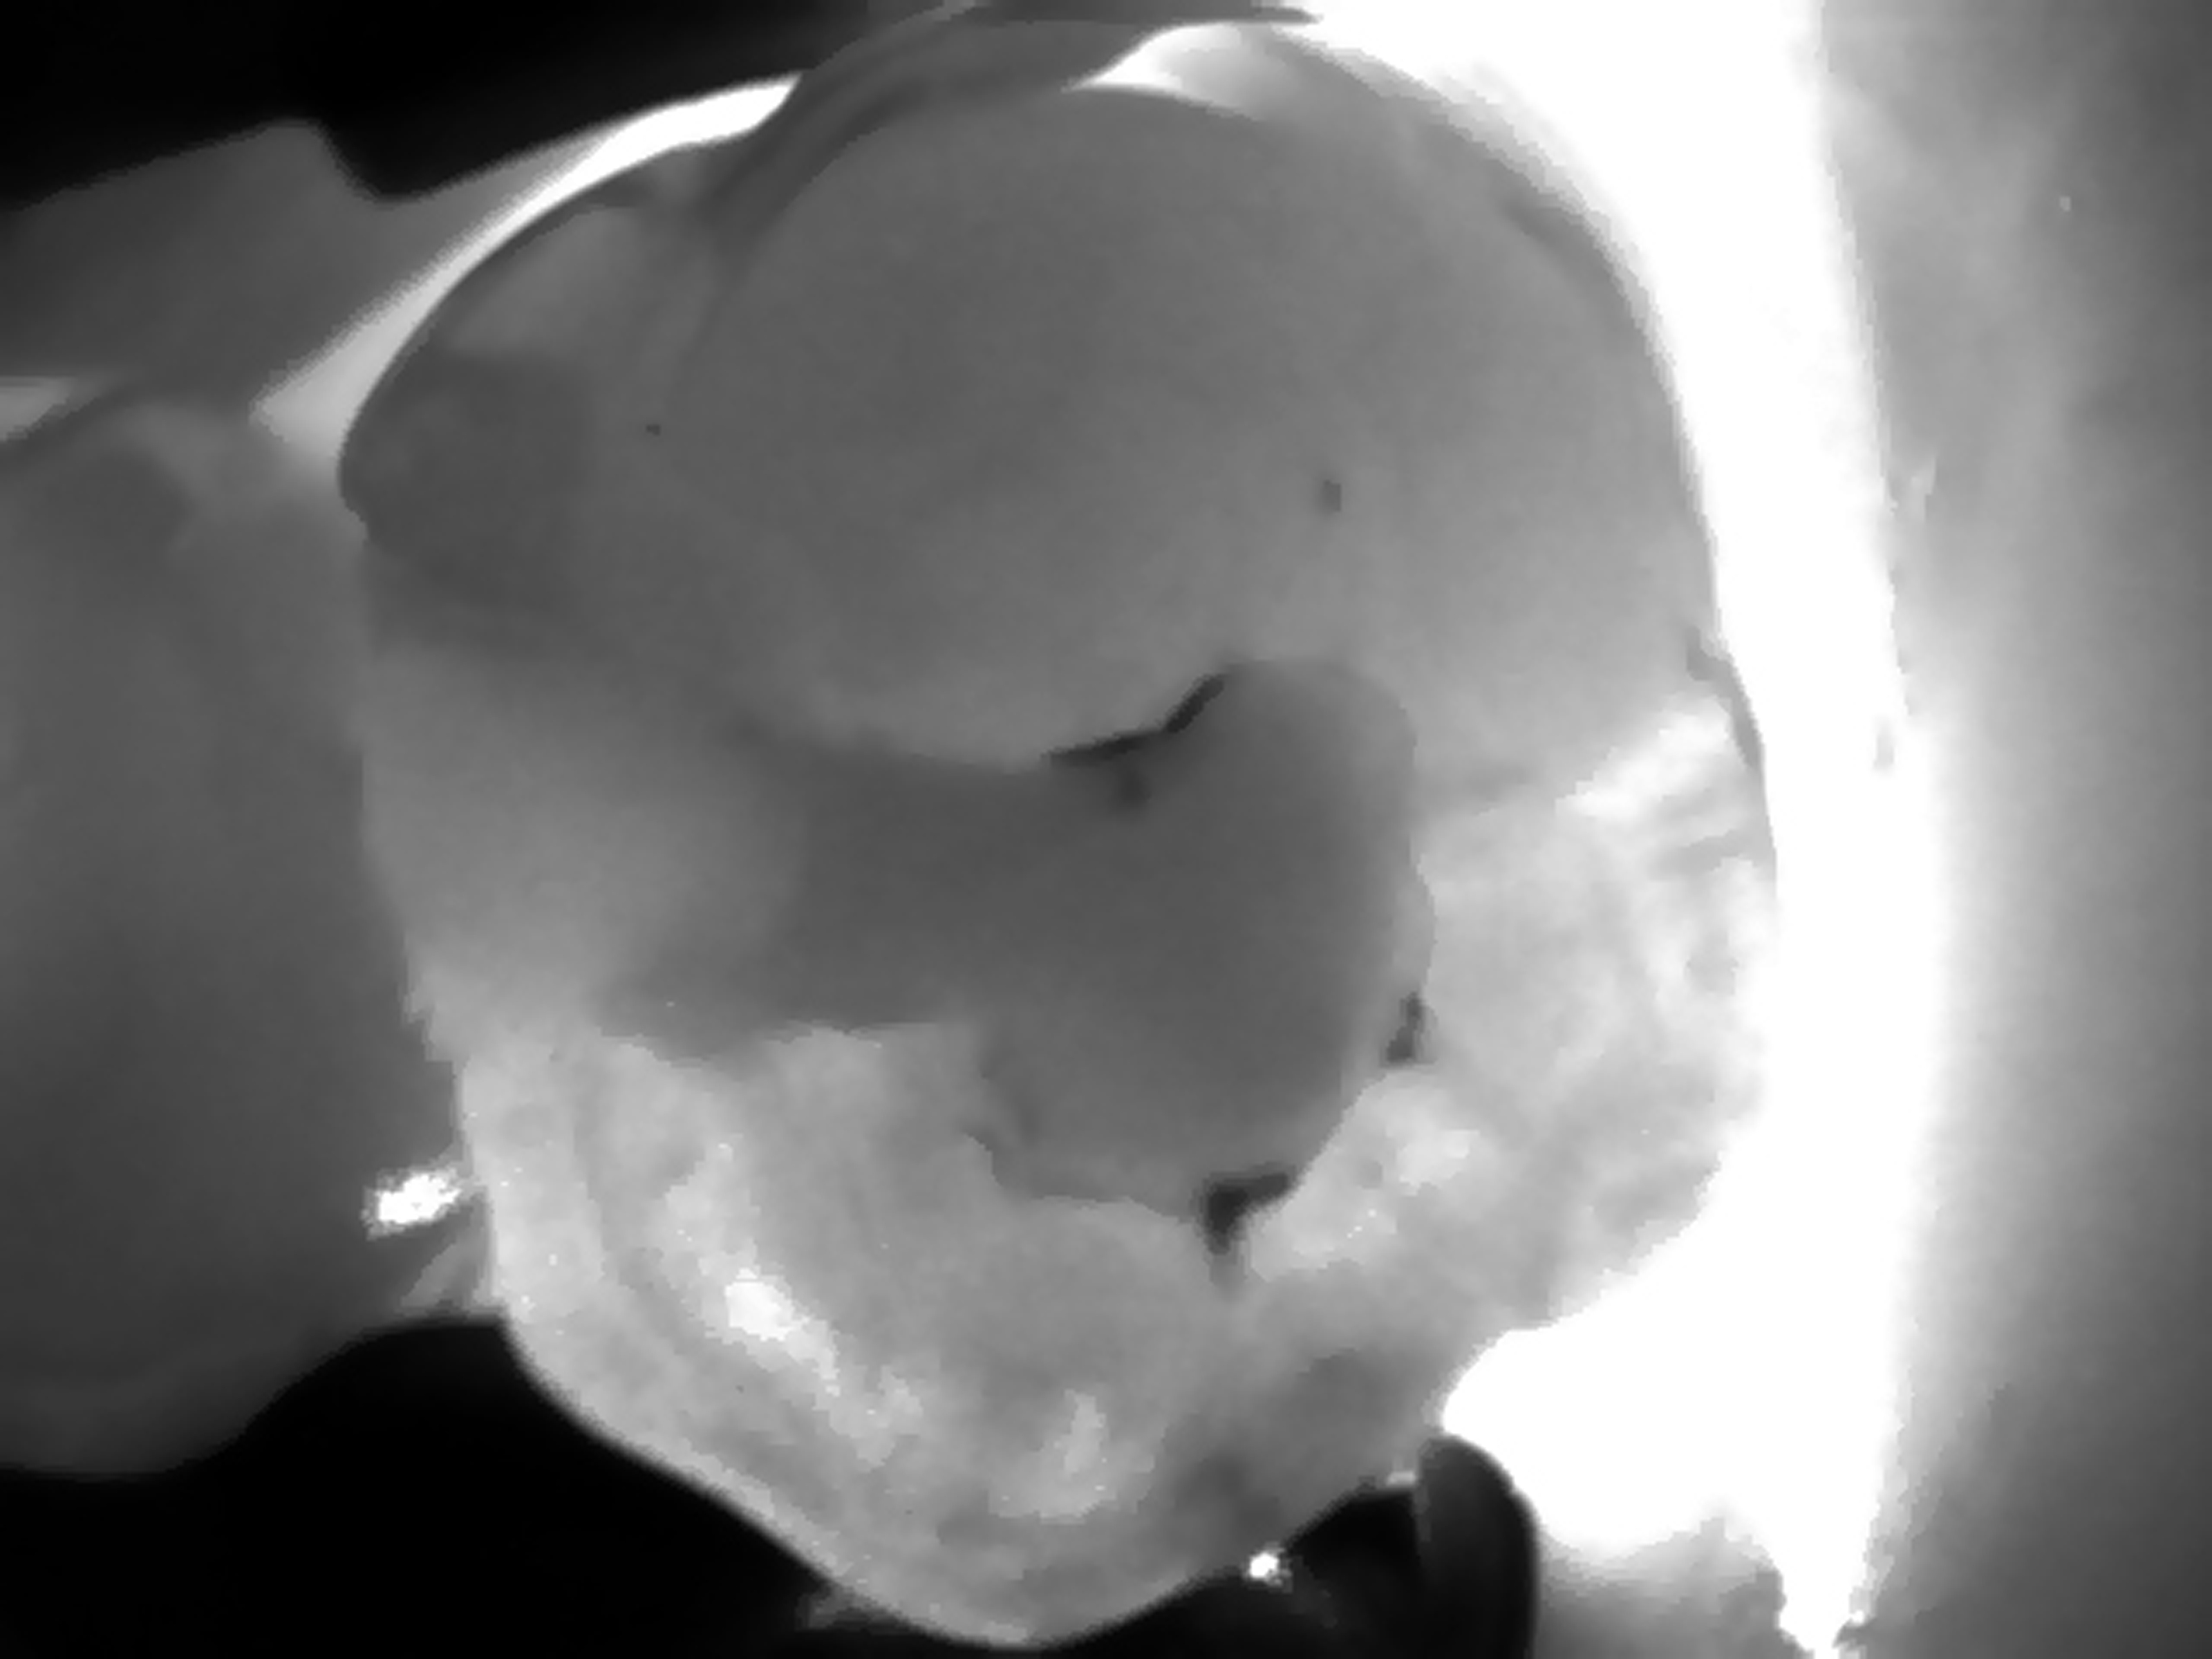

W przypadku wykrywania próchnicy wtórnej prezentowana metoda sprawdza się przy detekcji zmian spowodowanych nieszczelnością brzeżną wypełnień. Pozwala ona na diagnostykę wszystkich powierzchni zębów oraz na wykrywanie próchnicy wtórnej. Jednak najlepiej sprawdza się w wykrywaniu zmian próchnicowych na powierzchniach okluzyjnych i stycznych zębów. Zwłaszcza w przypadku powierzchni międzyzębowych wykazuje wyższą dokładność badania niż badanie radiologiczne, a dodatkowo jej użycie nie wymaga emisji promieniowania jonizującego, jest więc obojętne dla organizmu pacjenta. Nie ma żadnych przeciwwskazań do wykonywania badania, można je powtarzać dowolną ilość razy, zarówno u dzieci, jak i w przypadku kobiet w ciąży, czy też pacjentów z rozrusznikami serca.

Obraz prześwietlonego zęba trzonowego z próchnicą wtórną wokół wypełnienia na powierzchni okluzyjnej uzyskany w technologii NILT przy pomocy urządzenia DIAGNOcam (KaVo).